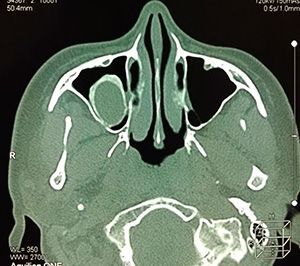

Диагностика кист

Простым осмотром обнаружить кисту невозможно. ЛОР-врач по совокупности жалоб и других данных может заподозрить, что у человека образовалась киста в придаточных пазухах.

• Рентгеновское исследование – определение взаимного расположения костей черепа и носовых пазух;

• Компьютерная томография – получение 3-мерного изображения;